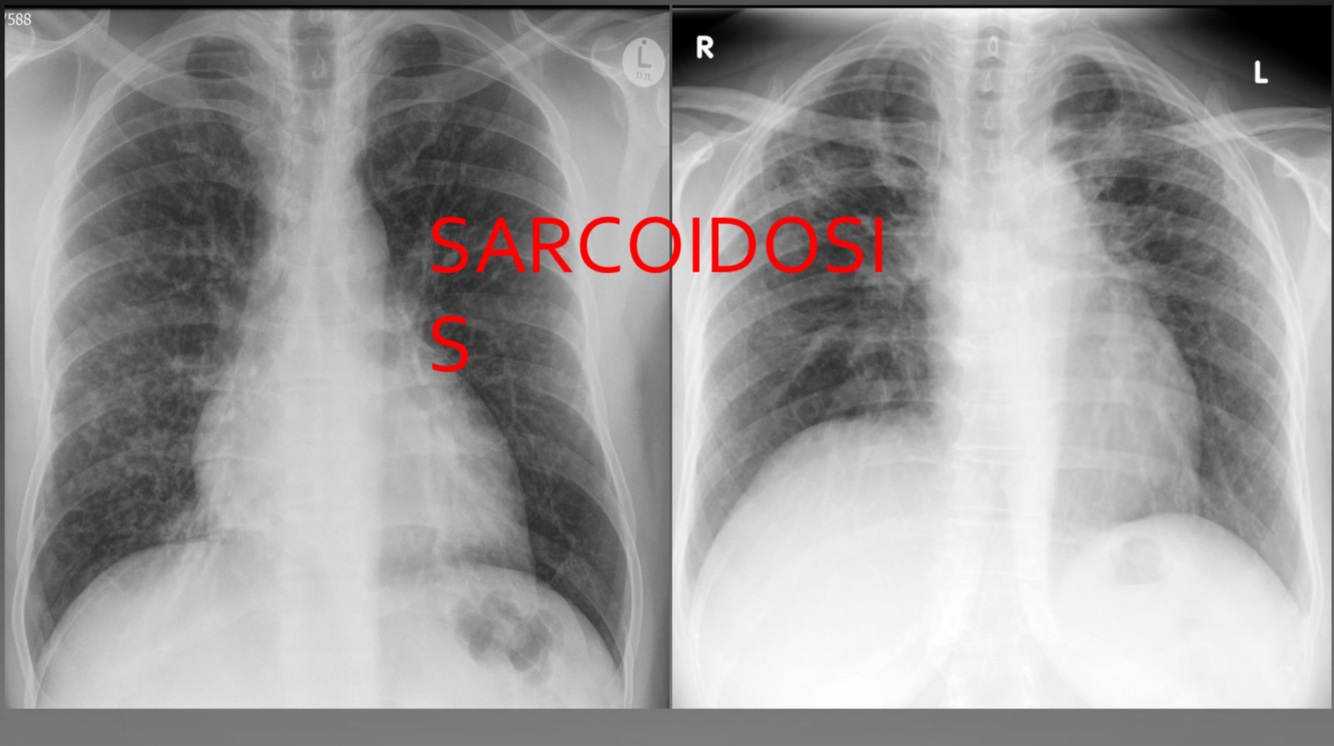

Mimics of TB

Sarcoidosis